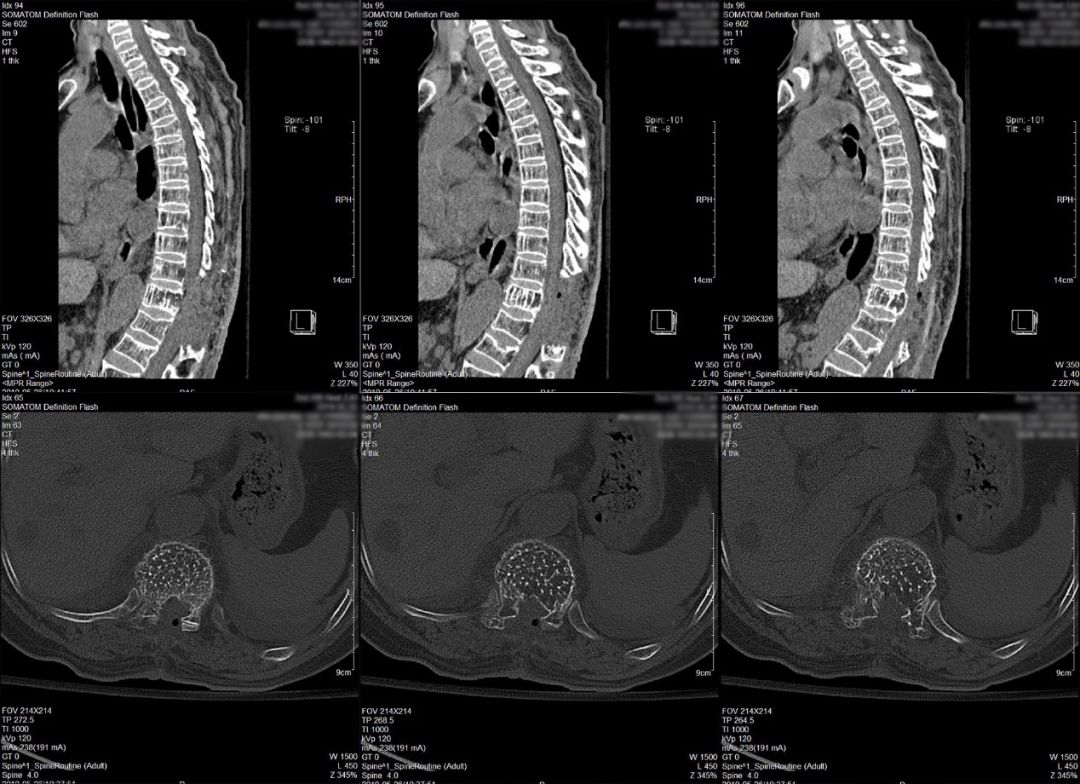

影像学检查:胸椎增强MRI提示胸11椎体及附件骨骨质破坏,呈膨胀性改变,椎体内间栅栏状纵行骨小梁存留(图1);胸椎CT平扫提示病变累及胸11全椎体及附件,表现为蜂窝样骨质改变。胸11椎体及两侧椎弓根、横突骨质密度减低,呈栅栏状改变,椎体向四周膨隆,椎管狭窄,椎旁软组织肿胀。胸12、腰1楔形变(图2)。

图2.术前胸椎CT平扫见胸11蜂窝样改变,提示血管瘤可能。